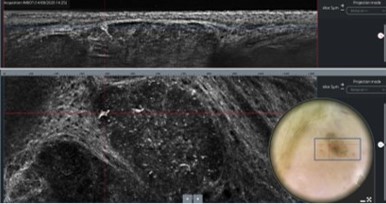

Click to view moreLeading imaging technologies advancing non-invasive dermatological diagnostics